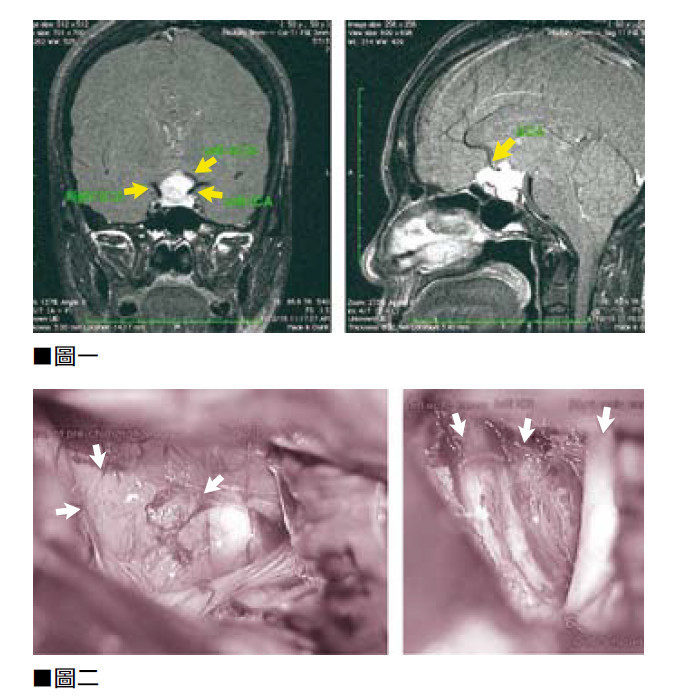

腦膜腫瘤導致病人腦幹和顱底第5至12條神經線受到壓迫和變形扭曲。(見圖三)症狀包括左側面部神經出現如觸電般的痺痛。病人接受了微創腦神經外科手術,在持續神經功能傳導的監測下,筆者進行了12小時的微創顯微鏡腦神經外科手術,將腫瘤完全切除。(見圖四)

因為腫瘤壓迫着腦幹和顱底神經線,尢其是將第7條(面部神經)及第8條(聽覺神經)的顱底腦神經線嚴重推移,以致神經線扭曲變形。在腫瘤切除手術過程中,筆者以1至2厘米的手指動作操作,其力度、方法及方向都要精準無誤,長時間集中精神從腫瘤的周邊和裏面尋找及保護神經線。

有關手術的風險,最常見的神經損傷就是永久失去聽力,或是暫時或永久性的臉部神經癱瘓。醫學文獻中有些病例,手術風險和併發症甚至會導致腦幹神經或血管受損,導致嚴重傷殘甚至死亡。幸運的是,這位病人所有顱底的腦神經線及其功能、微小血管,以及腦幹主要的基底動脈,全部均完好保存沒有損傷。